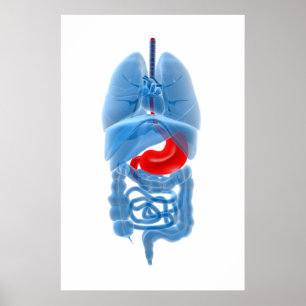

Human Internal Anatomy 1902 Print

Prijs€ 23,90